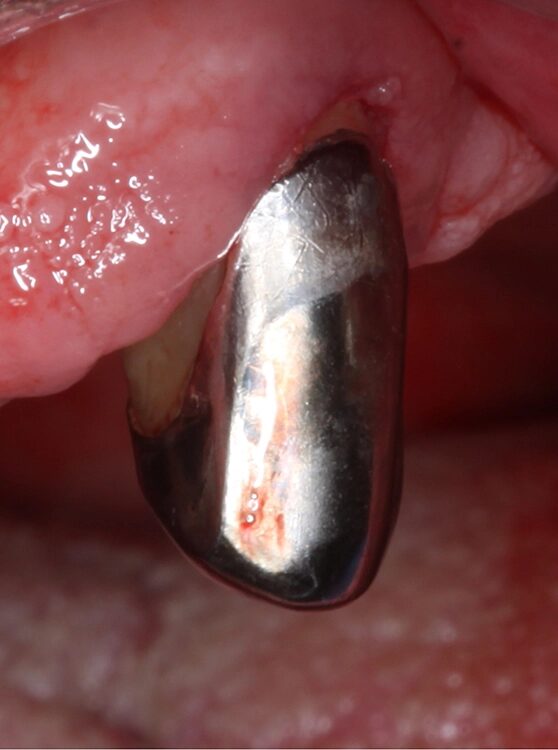

Der Patient wurde über die Krankheitsentstehung, die Prognosen der Einzelzähne und die therapeutischen Optionen aufgeklärt. Es wurde eine systematische parodontale Therapie unter Berücksichtigung der aktuellen EFP/ DGParo-Leitlinien geplant [48]. Der radiologisch sichtbare Knochenverlust an den Zähnen 37 und 47 ging bereits weit über den Apex hinaus. Eine parodontale Therapie erschien daher nicht mehr erfolgversprechend. Die Zähne wurden vor der antiinfektiösen Therapie (AIT) extrahiert und die Alveolen mit adaptierenden Nähten stabilisiert. Im Rahmen der Unterweisungen für eine optimierte häusliche Mundhygiene wurde dem Patienten die Benutzung einer Monobüschelbürste demonstriert und empfohlen. Bei regelmäßiger Anwendung an den vereinzelten, mit Primärteleskopen versorgten Zähnen lassen sich auch diese Zähne in ihrer gesamten Zirkumferenz sehr gut reinigen. Bei den verbliebenen 5 Zähnen war geplant, die zur Verfügung stehenden nichtchirurgischen Möglichkeiten auszuschöpfen. Eine adjuvante Gabe von systemischen Antibiotika war allerdings nicht vorgesehen. Das bedeutete aber, dass im Oberkiefer an den besonders schwer vorgeschädigten Zähnen 13 und 23 neben der subgingivalen Instrumentierung mit Ultraschall und Pulverwasserstrahl (EMS, Nyon, Schweiz) zusätzlich SMP (Straumann® Emdogain®, Basel, Schweiz) appliziert werden sollten [50]. Da beide Zähne einen erhöhten Lockerungsgrad aufwiesen, bestünde die Notwendigkeit einer präoperativen Schienung spätestens vor einer möglichen chirurgischen Stufe-3-Therapie.

Der Punkt, dass beide Zähne demzufolge wohl eher nicht unter optimalen Bedingungen parodontalchirurgisch operiert werden können, hat daher auch zu der Entscheidung einer SMP/EMD-Anwendung in der AIT beigetragen. Die AIT wurde an einem Termin durchgeführt. Nach der Applikation einer Lokalanästhesie wurden alle Zähne zunächst mit Ultraschall und nach Detektion glatter und harter Wurzeloberflächen mit einem erythritolhaltigen Pulverwasserstrahlgemisch mit dem Standard-Handstück behandelt (EMS, Nyon, Schweiz). An den Zähnen 13 und 23 wurden in derselben Sitzung noch zusätzlich SMP – entsprechend einem von Prof. A. Kašaj publiziertem Protokoll (Abb. 5) – appliziert. Zuvor wurde eine Blutstillung unter Verwendung von H2O2 und dem Einbringen von sterilisiertem Superfloss vorgenommen und ein EDTA-Gel zur Konditionierung der Wurzeloberfläche appliziert. Das Aufbringen von Histoacryl® (B. Braun, Tuttlingen, Deutschland) Gewebekleber zum Verschluss der instrumentierten parodontalen „Taschen“ rundete diesen Behandlungszyklus ab. Das detaillierte Vorgehen bei diesem Patienten ist in den Abbildungen 4a–j dargestellt. Da die Zähne nicht geschient werden konnten, wurde der Patient instruiert, auf ein Herausnehmen und Wiedereinsetzen der Prothese sofern möglich in den nächsten Tagen zu verzichten. Nach der AIT wurde die supragingivale Plaquekontrolle an 3 Terminen kontrolliert und die Wundheilung durch professionelle Zahnreinigungen unterstützt.

Die klinische und radiologische Untersuchung nach der AIT und der Applikation von Straumann® Emdogain® an den Zähnen 13 und 23 erfolgte nach 7 Monaten. Die Sondierungstiefen und die parodontal entzündete Wundfläche hatten sich deutlich reduziert (Abb. 6). Es lagen keine Sondierungstiefen >5 mm mehr vor. Auch radiologisch konnten Umbauvorgänge und Kortikalisierungen auf den Einzelbildern im Vergleich zur initialen Panoramaschichtaufnahme festgestellt werden. Somit bestand zu diesem Zeitpunkt keine Indikation für ein weiteres ggf. parodontalchirurgisches Vorgehen.